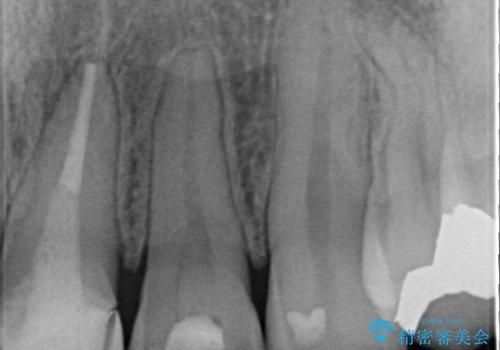

- 矯正前に仮歯にしていた前歯を矯正治療終了後にセラミックによる治療を希望された患者様です。

プラスチックのものから綺麗なセラミックになり喜んでいただきました。